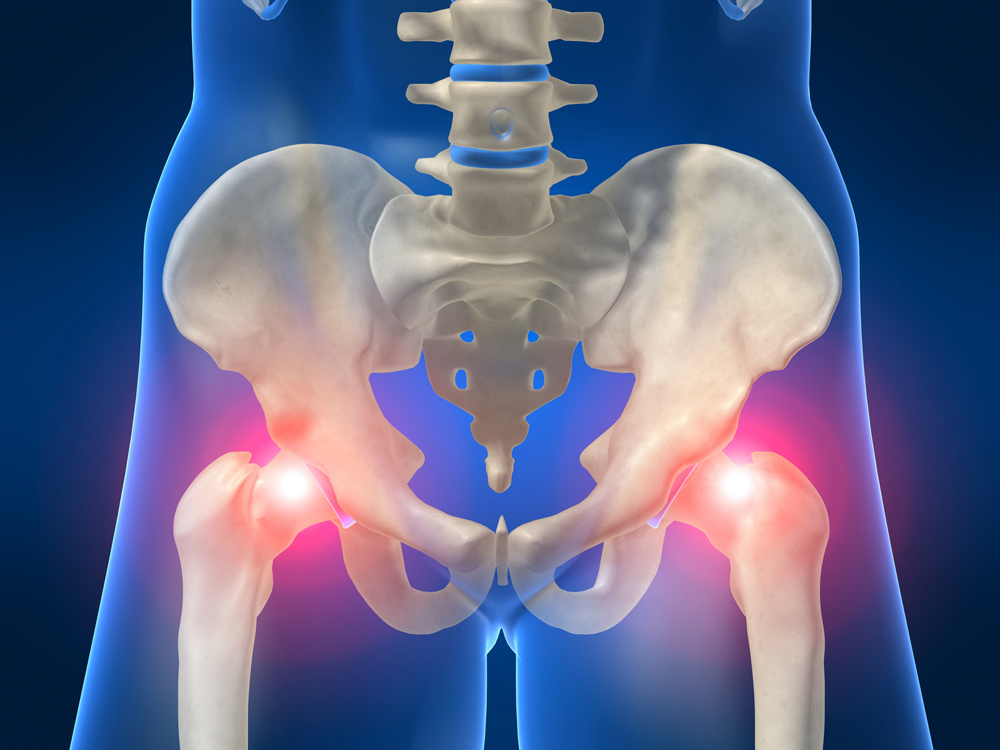

Тазобедренный сустав является местом соединения бедренной и тазовой кости и имеет шаровидную форму. Он отличается особой подвижностью и способностью переносить большие нагрузки. Данный сустав задействован на таких этапах движения как наклон и распрямление тела, передвижение ног в стороны и обратно, поворот ноги внутрь и наружу. Это достигается благодаря особенностям строения сустава: головка бедренной кости в тазу входит в вертлюжную впадину. Суставная капсула хорошо укреплена связками, которые образуют круговую зону.

Под переломами тазобедренного сустава понимают травмы головки, шейки бедренной кости и вертлужной впадины.